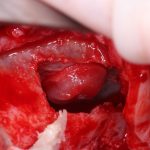

Я зафиксировал костный блок практически без адаптации на несколько винтов. Обрати внимание, что винты находятся в зоне, где не планируется установка имплантатов. Фиксация должна быть надежной, поскольку мне еще предстояла подготовка лунок для имплантатов. Трех винтов для этого вполне достаточно.

Дальнейшая адаптация костного блока свелась к сглаживанию острых краев. После чего я приступил к подготовке лунок и установке имплантатов.

Глянем на то, что получилось:

Осталось адаптировать костный блок (убрать острые края), проверить его фиксацию и, при необходимости, добавить винты. Десятисекундное дело.